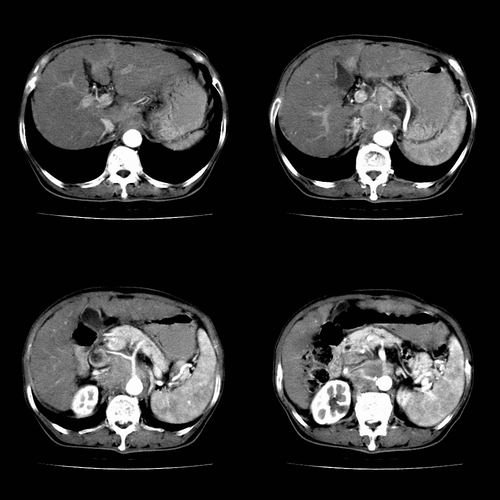

根据增强的特点看,应该是肝癌,腹膜后胰头区低密度占位应该是腹膜后淋巴结增大,多考虑转移

肝癌伴腹膜后淋巴结转移,肝硬化伴脾大,好像没有发现门静脉及下腔静脉瘤栓形成.看腹腔干是不是有浸润

典型肝硬化、肝脏右后叶肝癌。动脉期、静脉期很好,不知是否用高压注射器?

1、肝右叶肝癌,后腹膜淋巴结转移(包绕腹腔干及肠系膜上动脉,推压门静脉、下腔静脉及胰头)

2、肝硬化、脾肿大

3、右肾小囊肿

典型病例:

1、肝硬化,脾肿大

2、肝癌,动静脉瘘(动脉期门静脉内造影剂进入)

3、后腹膜淋巴结转移,下腔静脉推移